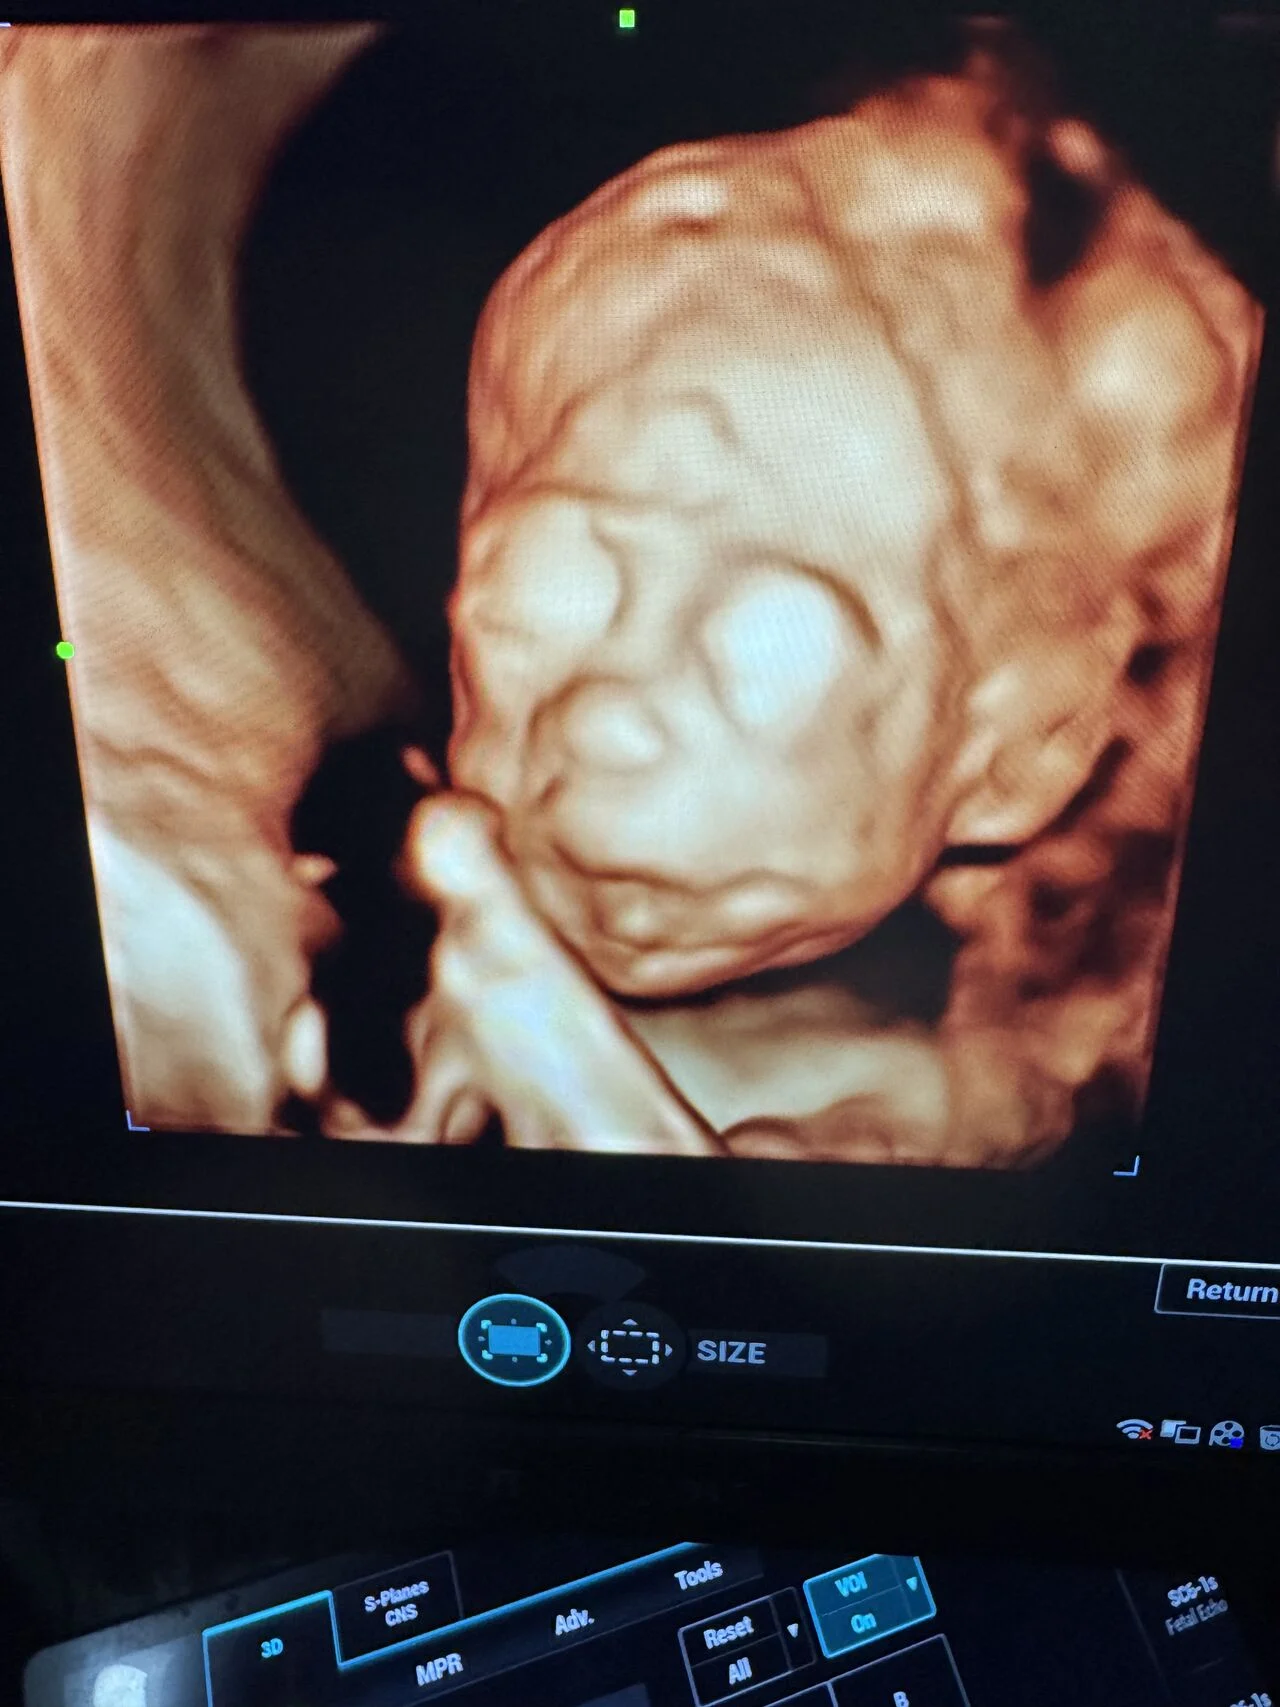

“Fetal Anomaly Case | Semilobar Holoprosencephaly

A prenatal ultrasound case demonstrating features of semilobar holoprosencephaly.

3D imaging revealed associated midline facial abnormalities.